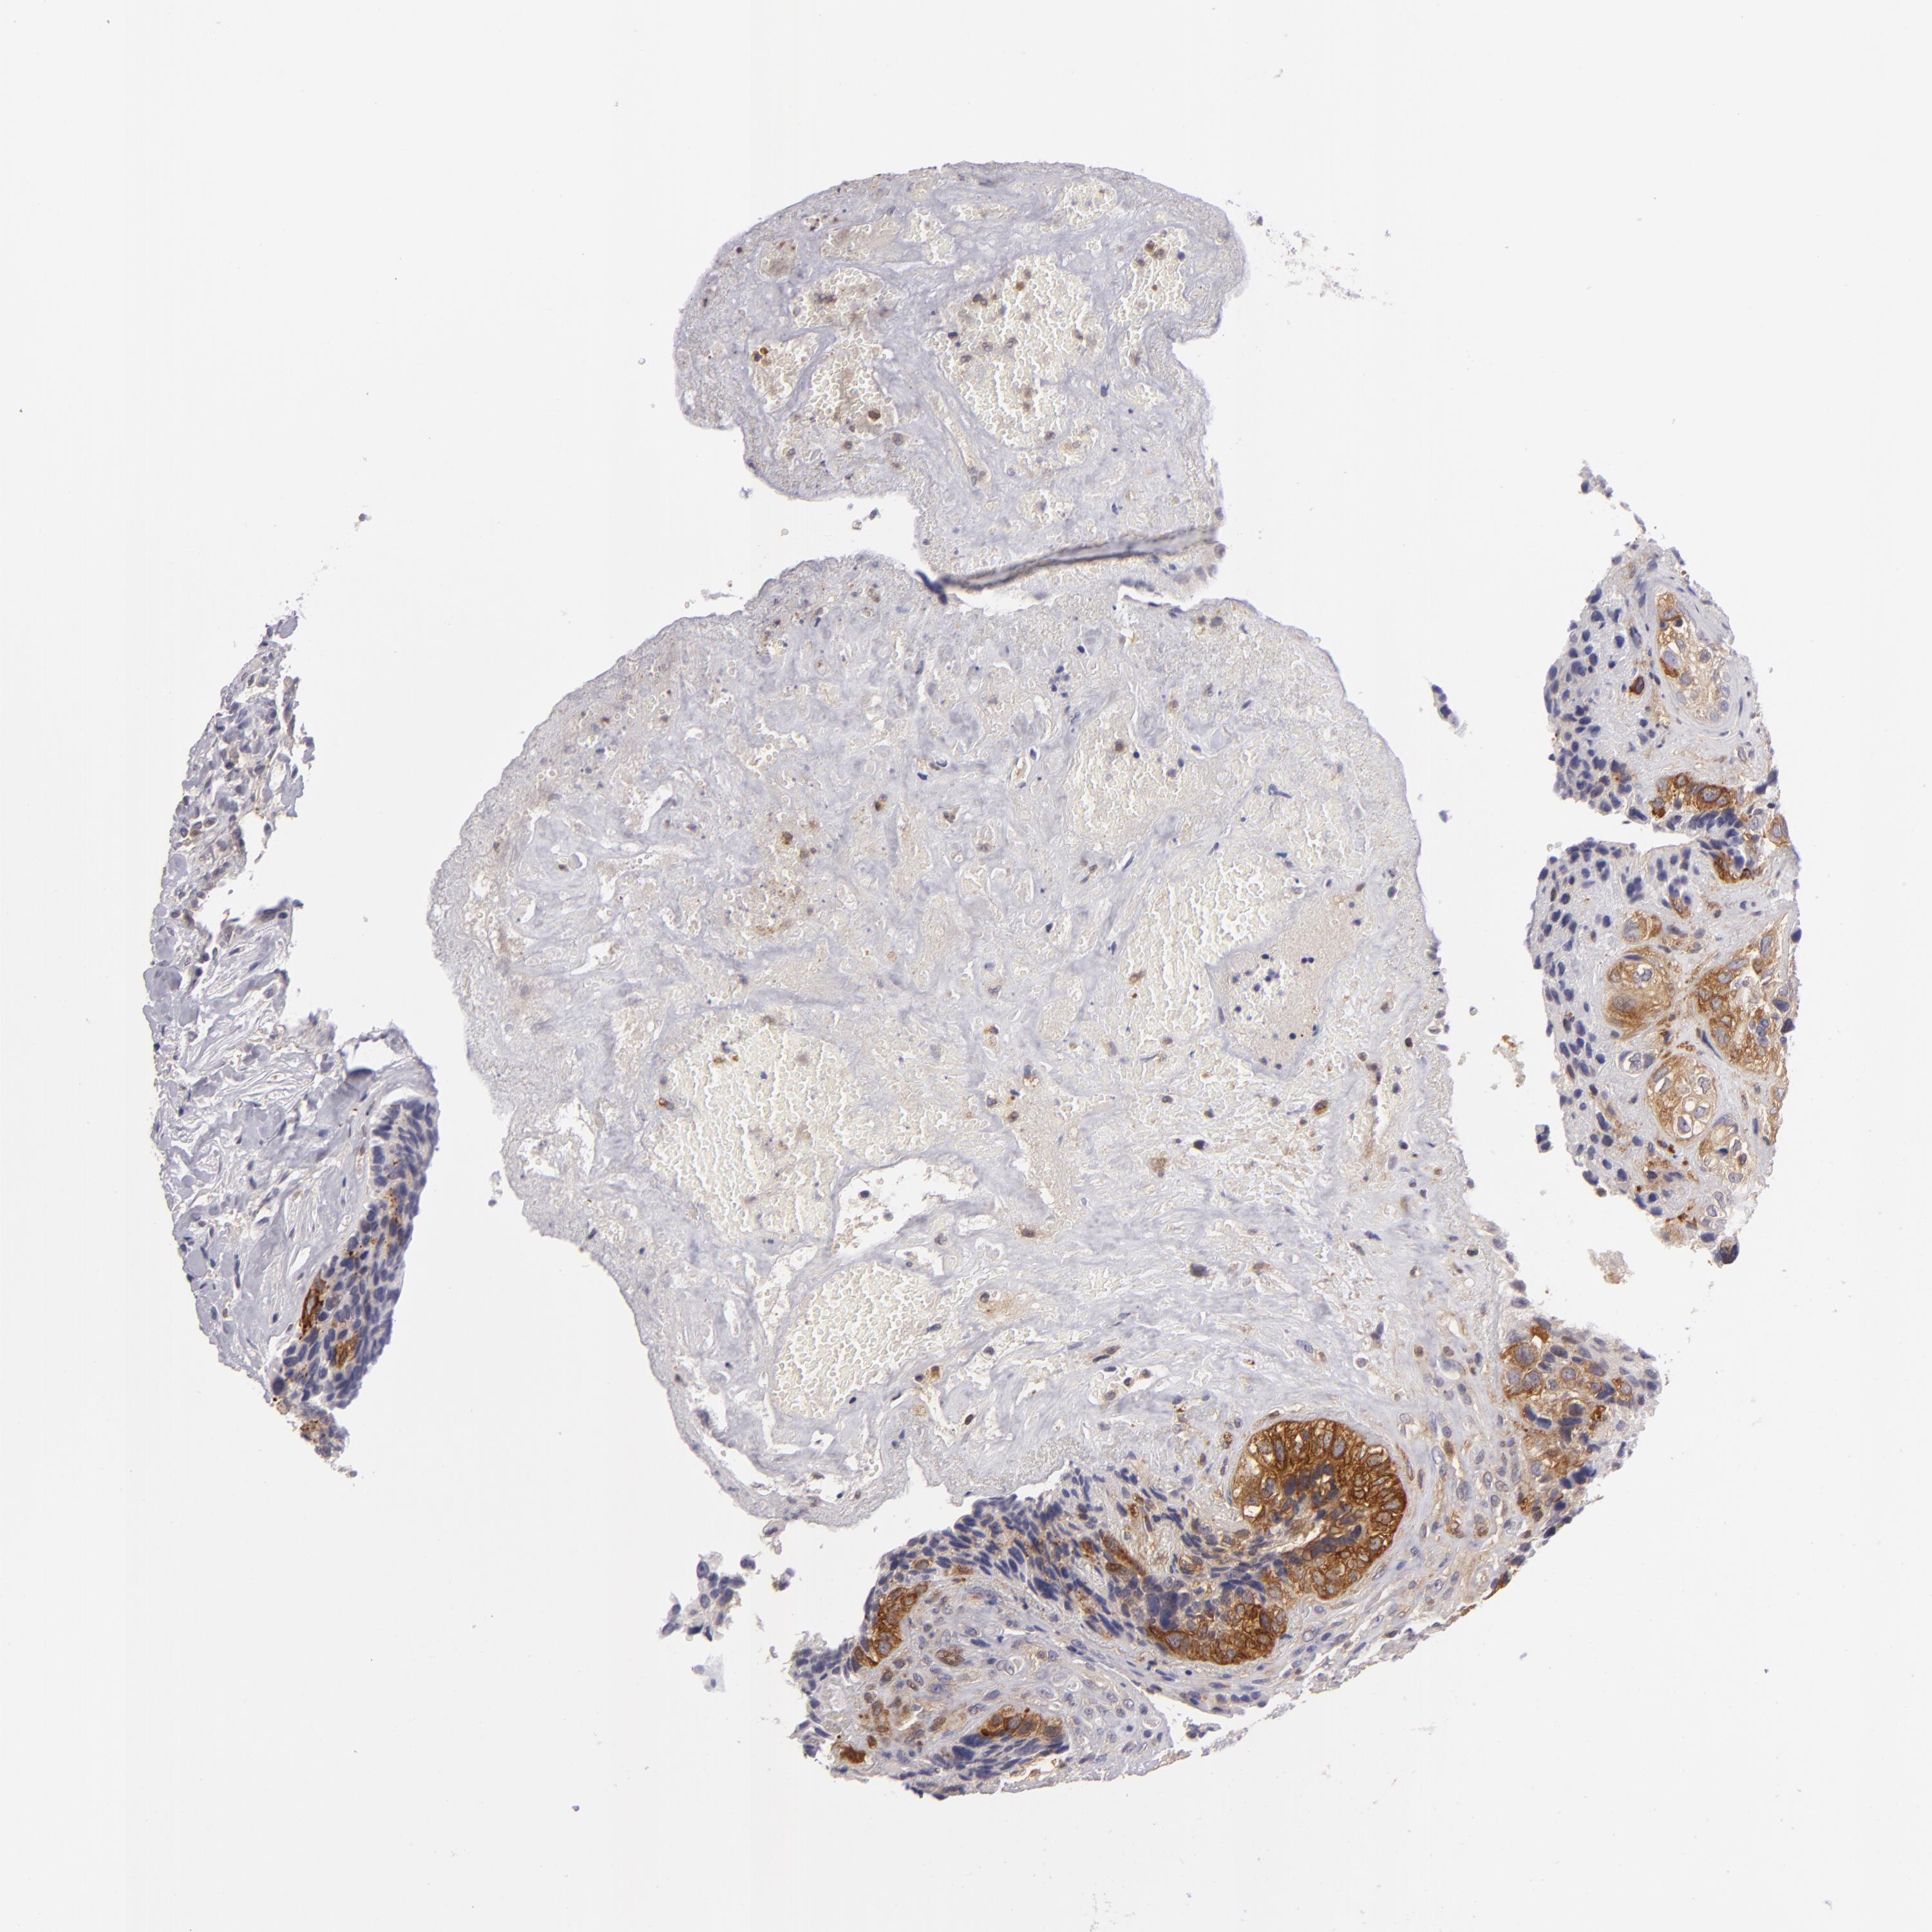

BRCA TCGA BRCA VALIDATION PROTEIN EXPRESSION

ANTIBODIES

AND

VALIDATION